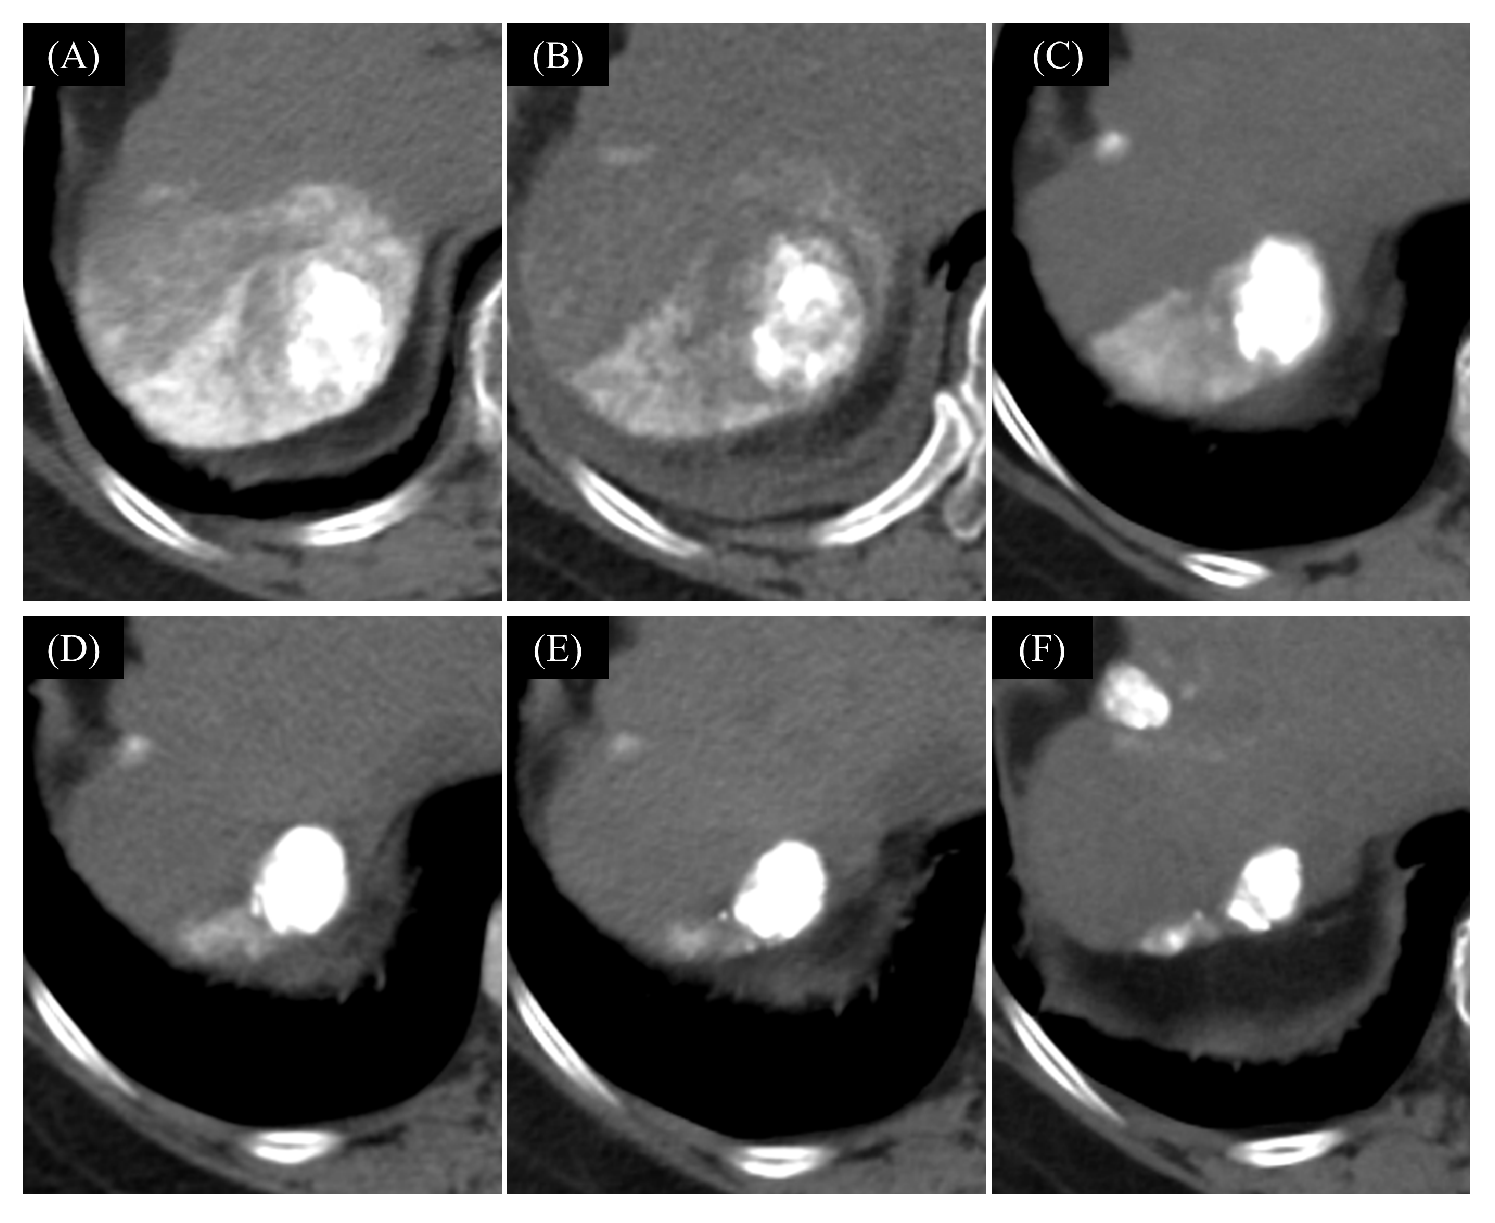

2.5.1. The Changes of Tumor Hemodynamics

3.2. The Change of Tumor Hemodynamics